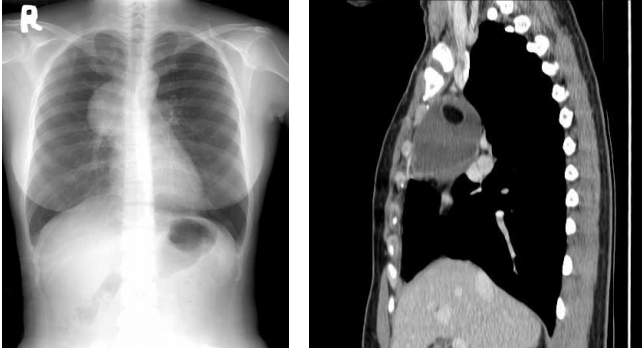

80 一位 8 歲女童,主訴胸悶、胸部 X 光片及 CT 如圖示,最正確的診斷應為:

(A)淋巴瘤 (B)畸胎瘤(teratoma) (C)胸腺瘤(thymoma) (D)胸腺囊腫(thymic cyst)